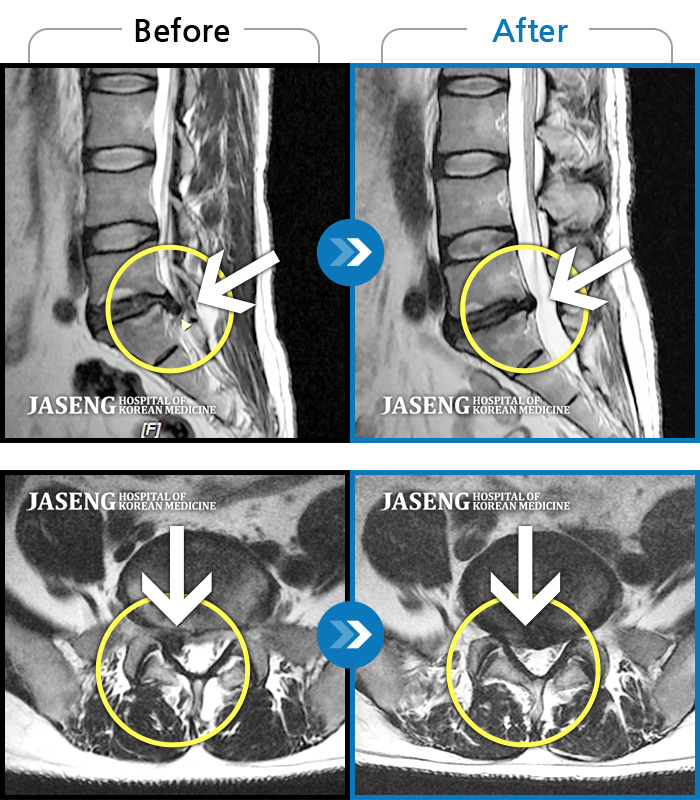

Before

After

환자에게 사전 동의를 받아 동일 조건에서 촬영되었습니다.

개인에 따라 치료 후 부작용이 발생할 수 있으니 의료진과 상담 후 치료를 진행하시기 바랍니다.

서 있거나 움직일 때 좌측 골반통증 및 좌측 하지 방사통과 발바닥 저림

오른 다리 통증, 야간통